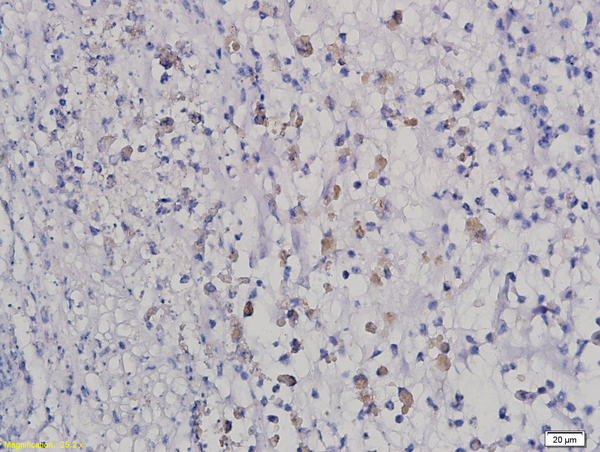

IHC-P analysis of rat intestine tissue using GTX51728 HOXB8 antibody.